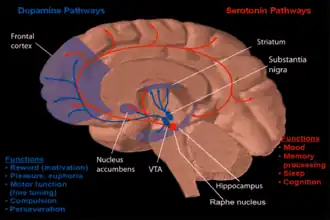

Dopamine and serotonin

Dopamine and serotonin -

The nucleus accumbens (NAc or NAcc; also known as the accumbens nucleus, or formerly as the nucleus accumbens septi, Latin for 'nucleus adjacent to the septum') is a region in the basal forebrain rostral to the preoptic area of the hypothalamus.[1] The nucleus accumbens and the olfactory tubercle collectively form the ventral striatum. The ventral striatum and dorsal striatum collectively form the striatum, which is the main component of the basal ganglia.[2] The dopaminergic neurons of the mesolimbic pathway project onto the GABAergic medium spiny neurons of the nucleus accumbens and olfactory tubercle.[3][4] Each cerebral hemisphere has its own nucleus accumbens, which can be divided into two structures: the nucleus accumbens core and the nucleus accumbens shell. These substructures have different morphology and functions.

Major glutamatergic inputs to the nucleus accumbens include the prefrontal cortex (particularly the prelimbic cortex and infralimbic cortex), basolateral amygdala, ventral hippocampus, thalamic nuclei (specifically the midline thalamic nuclei and intralaminar nuclei of the thalamus), and glutamatergic projections from the ventral tegmental area (VTA).[18] The nucleus accumbens receives dopaminergic inputs from the ventral tegmental area, which connect via the mesolimbic pathway. The nucleus accumbens is often described as one part of a cortico-basal ganglia-thalamo-cortical loop.[19]

Dopaminergic inputs from the VTA modulate the activity of GABAergic neurons within the nucleus accumbens. These neurons are activated directly or indirectly by euphoriant drugs (e.g., amphetamine, opiates, etc.) and by participating in rewarding experiences (e.g., sex, music, exercise, etc.).[20][21]

The output neurons of the nucleus accumbens send axonal projections to the basal ganglia and the ventral analog of the globus pallidus, known as the ventral pallidum (VP). The VP, in turn, projects to the medial dorsal nucleus of the dorsal thalamus, which projects to the prefrontal cortex as well as back to the ventral and to dorsal striatum. Other efferents from the nucleus accumbens include connections with the tail of the ventral tegmental area,[24] substantia nigra, and the reticular formation of the pons.[1]